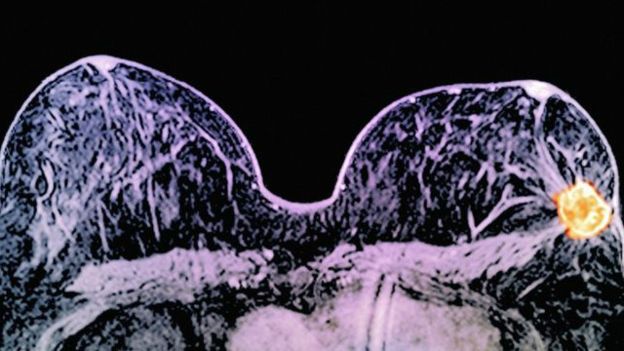

Doktorlar, tümörün teşhisinden ameliyat aşamasına kadar olan kısa süre içinde ilaçların kansere nasıl etki ettiğini araştırıyordu.

Ameliyat zamanı geldiğinde bazı hastalarda tümör ortadan kaybolmuştu.

Araştırmada tümör büyüklükleri 1 ila 3 cm olan kadınlara tedavi uygulandı.

İki haftadan daha kısa süren tedavide, vakaların yüzde 11'inde kanser tümüyle kaybolurken, yüzde 17'sinde 5 mm'den daha küçük hale geldi.